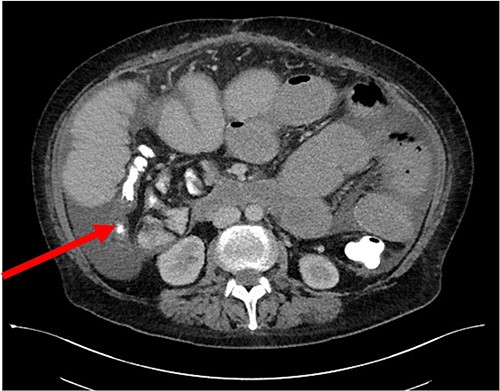

Her case was reviewed by a bariatric surgeon, who noted an internal hernia on CT causing the recurrent obstruction and subsequently planned for surgery (see Figs 2 and 3). On day 6, at the time of consenting for the procedure, she had a rapid neurological deterioration with fluctuating levels of consciousness (GCS10- E4V1M5), complete aphasia, bilaterally dilated pupils (9–10 mm), increased tone, hyper-reflexia and sustained clonus of 10+ beats in lower limbs. A broad list of differentials was considered due to her medical history. CT (Brain, head and neck angiogram and Venogram) scans reported no acute intracranial pathology, plasma ammonia level was 290 μmol/L (<50 μmol/L) (see Fig. 4), C-reactive protein (CRP) 44 mg/L (<10 mg/L) and ketosis with no acidosis.